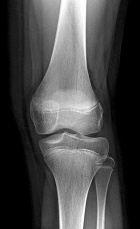

K.M. - 13 year old female with a painful soft tissue mass of the left anterior knee